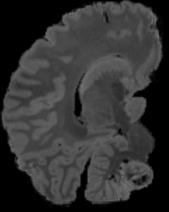

In neuroimaging, MRI tissue properties characterize underlying neurobiology, provide quantitative biomarkers for neurological disease detection and analysis, and can be used to synthesize arbitrary MRI contrasts. Estimating tissue properties from a single scan session using a protocol available on all clinical scanners promises to reduce scan time and cost, enable quantitative analysis in routine clinical scans and provide scan-independent biomarkers of disease. However, existing tissue properties estimation methods - most often $\mathbf{T_1}$ relaxation, $\mathbf{T_2^*}$ relaxation, and proton density ($\mathbf{PD}$) - require data from multiple scan sessions and cannot estimate all properties from a single clinically available MRI protocol such as the multiecho MRI scan. In addition, the widespread use of non-standard acquisition parameters across clinical imaging sites require estimation methods that can generalize across varying scanner parameters. However, existing learning methods are acquisition protocol specific and cannot estimate from heterogenous clinical data from different imaging sites. In this work we propose an unsupervised deep-learning strategy that employs MRI physics to estimate all three tissue properties from a single multiecho MRI scan session, and generalizes across varying acquisition parameters. The proposed strategy optimizes accurate synthesis of new MRI contrasts from estimated latent tissue properties, enabling unsupervised training, we also employ random acquisition parameters during training to achieve acquisition generalization. We provide the first demonstration of estimating all tissue properties from a single multiecho scan session. We demonstrate improved accuracy and generalizability for tissue property estimation and MRI synthesis.